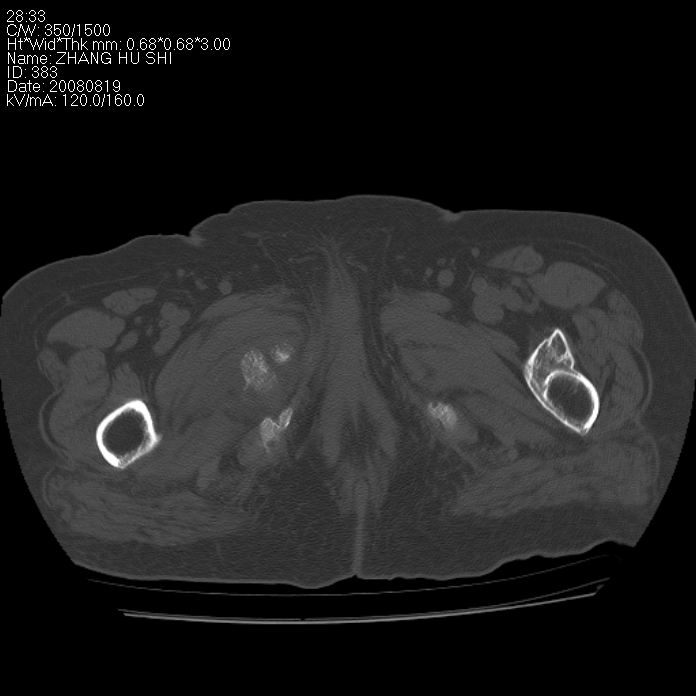

标题: CT15287:女 93岁 右髋关节疼痛 原左侧粗隆间骨折 CT发现右耻 [打印本页]

标题: CT15287:女 93岁 右髋关节疼痛 原左侧粗隆间骨折 CT发现右耻

支持转移

支持转移并周围软组织侵犯右闭孔内肌侵犯,但tb不能完全除外。